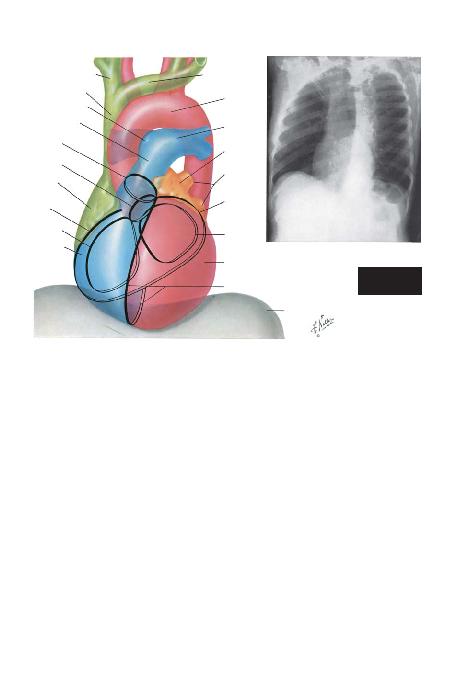

BÖLÜM I -- LEVHA 23

(Sayfa 23'ün devam>)

SA/ BRAK

SOL BRAK

AORTA

SOL ATR

SOL VENTR

D

SOL PULMONER

ARTER

VENLER

ATRKÜLER SULKUS

MHALKASI

SUPER

SA/ PULMONER ARTER

PULMONER TRUNK

SA/ ATR

SA/ VENTR

PULMONER

KAPAK HALKASI

AORT KAPA/I

HALKASI

ATRSULKUS

TRHALKASI

KALBANTERRADYOGRAMININ

YORUMLANMASI